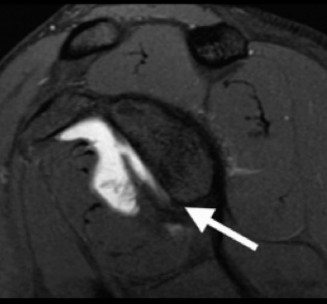

Which of the following findings is indicative of a subscapularis tendon tear?

The answer is (B). As the four layers of the lateral rotator interval insert onto the lesser tuberosity of the humerus, they form the “reflection pulley” that forms a sling around the tendon of the long head of the biceps before it enters the bicipital (intertubercular) groove. A tear of the upper part of the subscapularis can disrupt this reflection pulley and destabilize the biceps tendon, allowing it to sublux or even

dislocate out of its groove, usually in a medial direction. If this happens, the intertubercular groove will be empty on MRI. Often, a “pulley sign” will also be seen on MRI when this occurs. This is when contrast material extravasates extra-articularly just over the superior border of the subscapularis tendon on axial images (see Fig. 2–11).

Figure 2–11_Axial T1 MRI. Left: an empty intertubercular sulcus, positive pulley sign (straight _black arrow on left), and dislocated biceps tendon (curved black arrow). Right: fraying subscapularis tendon (arrow). (From Lyons RP, Green A. Subscapularis tendon tears. J Am Acad Orthop Surg. 2005;13(5):353–363.)

A high riding humeral head on plain films (Answer A) is associated with a massive rotator cuff tear and is the first sign of progression to cuff tear arthropathy that is seen on plain film.